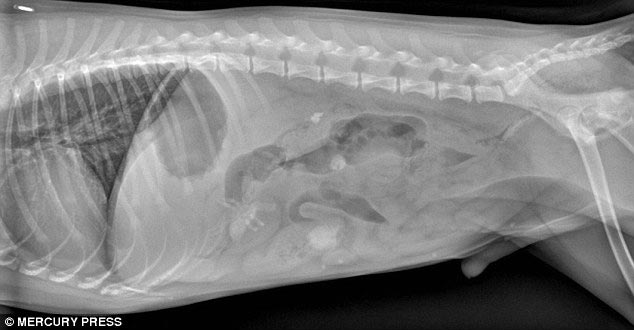

1 место - доберман Зевс, съевший 26 мячей для гольфа

![Что на ужин? Рентгеновские снимки животных, с шокирующими предметами извлеченными из их желудков предметы извлеченные из желудков животных, рентгеновские снимки животных съевших предметы, необычные предметы съели животные]()

Все 26 мячей извлеченные из его живота